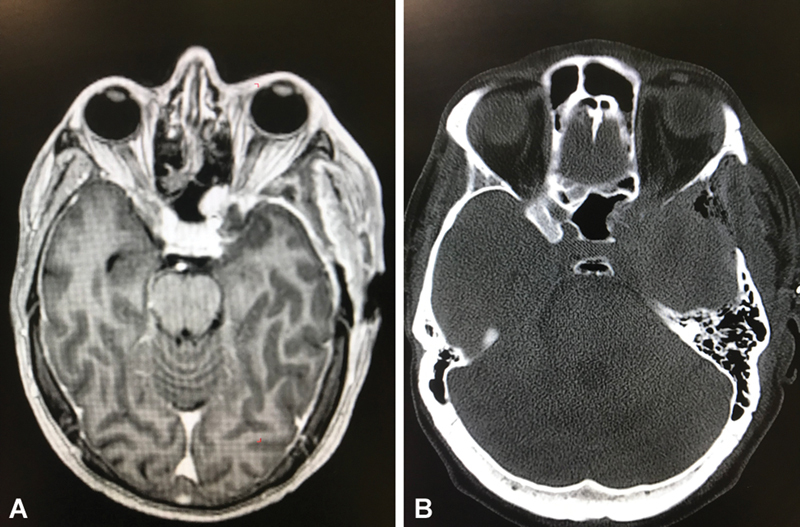

Anterior clinoid process metastases are rare. We present an unusual case of anterior clinoid process metastasis with sudden deterioration of visual function requiring emergency optic nerve decompression, resulting in recovery of visual function. The patient was a 41-year-old man with a diagnosis of leiomyosarcoma of the radius, operated on in 2014, with bone and lung metastases, who had been treated with chemotherapy and appeared to have stable disease at his last follow-up. Six years later, he developed a 1-month history of progressive unilateral loss of visual acuity and visual field defect (initially quadrantanopia that progressed to nasal hemianopia). Brain imaging showed a contrast-enhancing lesion affecting the left anterior clinoid process with extension to the cavernous sinus and sphenoid sinus, causing compression of the left optic nerve. Although the lesion could have suggested a meningioma given the location, in the context of the patient's oncological history, the diagnosis of metastasis was considered more likely. The patient was admitted to the hospital and, during the hospital stay, developed sudden left retro-orbital pain progressing to left amaurosis over approximately 8 hours. Urgent surgery was performed: a pterional craniotomy with partial tumor removal and optic nerve decompression with extradural anterior clinoidectomy. After surgery, the patient had an immediate but partial improvement in visual acuity and in the visual field defect. Metastasis to the anterior clinoid process is very uncommon, with only one case previously reported in the literature. In cases of visual impairment, symptoms may deteriorate rapidly to complete loss of vision, so urgent decompressive surgery of the optic pathway may be indicated to recover visual function, although recovery may be partial.